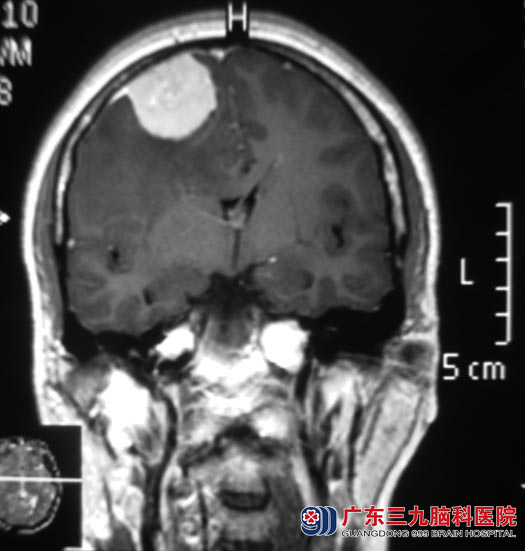

近期伴有头痛,当地医院CT检查提示右侧额部占位,考虑脑肿瘤。广东三九脑科医院头颅MR检查提示右侧额部占位,大小约33.4mm×33.5mm×39.1mm。

12月4日,鲁明主任主刀,在全麻下行右侧额部凸面脑膜瘤切除术,术中见硬膜下与硬膜粘连紧密的肿瘤组织,灰红色、质韧、血供丰富、与周围边界清楚,显微镜下达辛普森I级切除。现已康复出院。病理结果为:过渡型脑膜瘤(WHO I 级)。

▲手术前